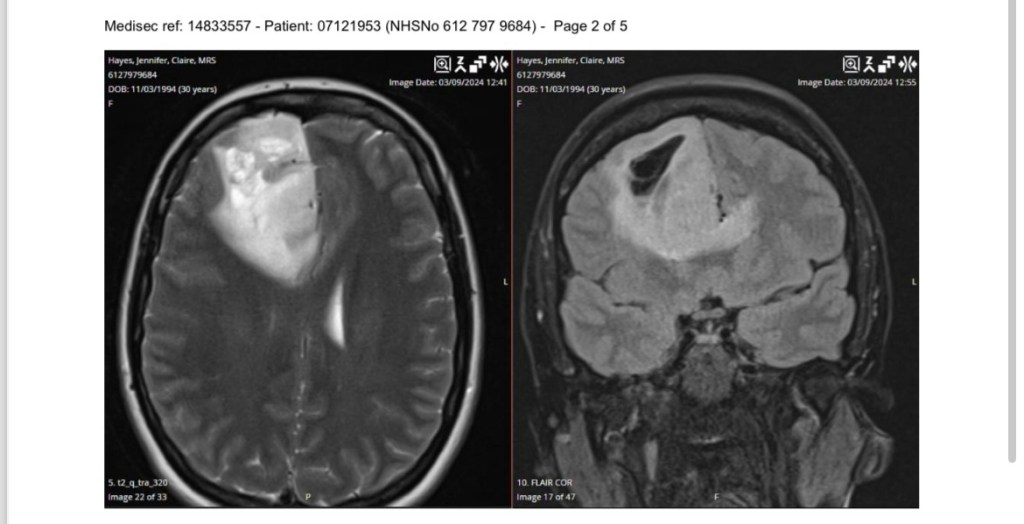

My picture for the end of this one is of big Nev himself. I was weird and requested a picture of him. The doctor said he’s never been asked that before 😂 It’s not a nice image obviously – but take a scroll down if you’re curious and weird like me. He’s massive. And he’s out stayed his welcome now. Does he not know anything about consent? It’s really not on to just start growing in someone’s head without asking first 🙄